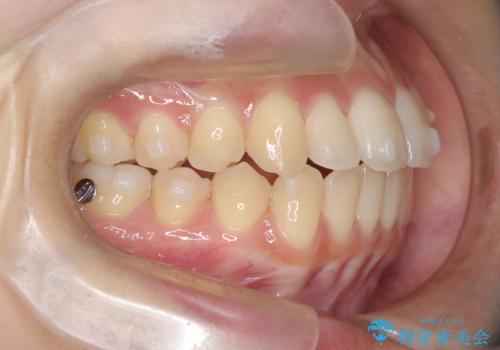

前歯のデコボコと突出を、目立たない矯正で解消

- 前歯のガタガタ(叢生)と、前歯が出ている(突出している)ことを気にされてご来院されました。精密な検査の結果、歯が並ぶスペースと、前歯を引っ込めるスペースの両方が不足していると診断。患者様のご希望に合わせ、透明で目立ちにくいインビザライン(マウスピース矯正)による治療計画を立案しました。スペースの確保は、奥歯全体を奥へ動かす遠心移動と、歯の側面をわずかに削る**IPR(歯間乳頭保護下ストリッピング)**を組み合わせて行い、前歯を効果的に引っ込めることを目指します。

今回の矯正治療では、透明なマウスピース型の装置インビザラインを使用しました。前歯を無理なく引っ込めるスペースを作るため、まず奥歯全体を後方へ移動させる遠心移動を実施。さらに、安全性が確保できる範囲で歯の側面をわずかに削るIPRを併用し、必要なスペースを確保しました。これらの処置により、前歯のデコボコが解消され、前に出ていた前歯も適切に引っ込みました。目立たない装置で治療を完結することで、叢生と突出感が解消され、機能性と審美性が向上した美しい口元を獲得していただけました。